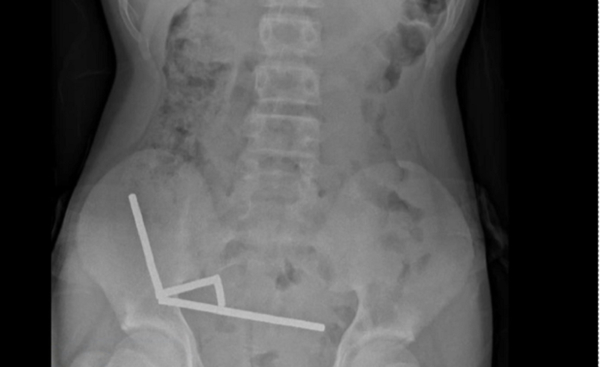

Αμέσως ειδοποιήθηκε ασθενοφόρο του ΕΚΑΒ και ο εργαζόμενος μεταφέρθηκε στο Νοσοκομείο-Κέντρο Υγείας Νάξου όπου διαγνώστηκε με σπάσιμο στο πόδι και κρίθηκε αναγκαία η διακομιδή του σε νοσοκομείο των Αθηνών ώστε να χειρουργηθεί. Την ίδια ώρα ο συνάδελφός του και πρόεδρος του Σωματείου των εργαζομένων στο δήμο Νάξου και Μικρών Κυκλάδων Βαγγέλης Κατερίνης κλήθηκε από τον Αστυνομικό Σταθμό Φιλωτίου ώστε να δώσει κατάθεση για το συμβάν. Σε δήλωση του στο naxostimes.gr ο κ. Κατερίνης ανέφερε ότι ο τραυματισμός του συναδέλφου του είναι σοβαρός και ότι ο ίδιος κατέθεσε στον Α.Σ. Φιλωτίου σχετικά με το συμβάν. Σημείωσε παράλληλα ότι άμεσα ενημερώθηκε και η δημοτική αρχή.